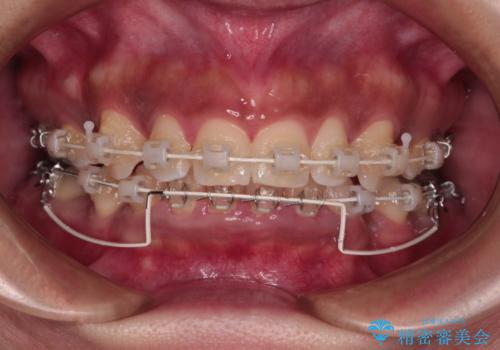

- 矯正装置

- 審美装置

- 下顎前歯部には叢生が認められ、口を自然に閉じにくい状態でした。また、噛み合わせが深い「ディープバイト」の状態で、見た目だけでなく将来的な奥歯への負担も懸念されました。

口元の突出感を改善するため、上下左右の小臼歯4本を抜歯する矯正治療を計画しました。

「矯正装置が目立つのは避けたい」というご希望があったため、プラスチックブラケット+コーティングワイヤーを使用した審美装置を選択しました。